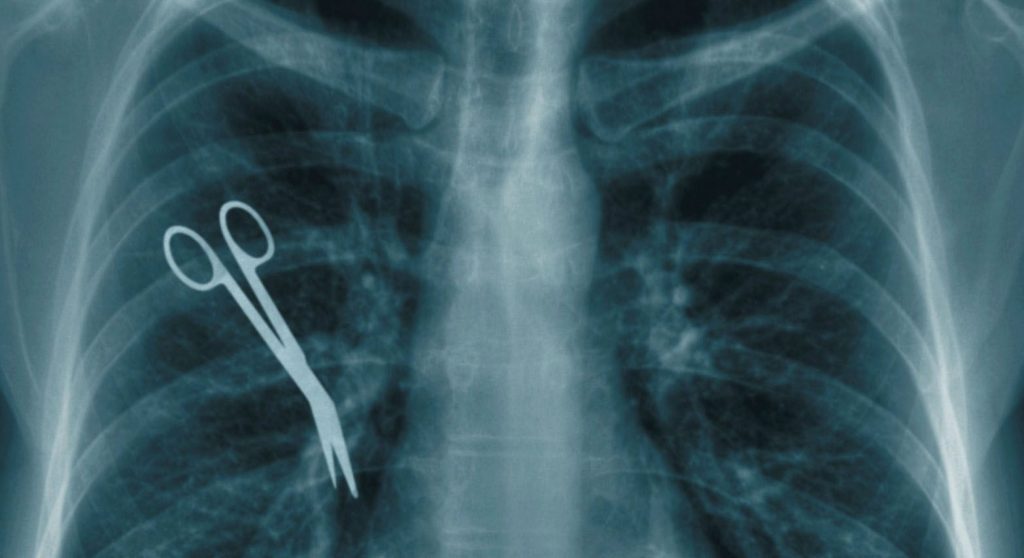

Οι υποθέσεις αφορούν ιατρικά λάθη από παραλείψεις ή εσφαλμένες πράξεις, όπως π.χ.:

- Άλλες λανθασμένες ενέργειες, ιδιαίτερα σε περιπτώσεις χειρουργείων.